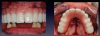

Fig 18. Preoperative photograph of a patient of mature age who desired a fixed alternative treatment option.

Figure 18

A sophisticated and technologically innovative alternative to rejuvenating a terminal smile and providing a more youthful and natural smile is a complete full-arch fixed screw-retained bridge. The mature-age population that most represents the request for fixed alternative treatment options is the 55- to 75-year-old group17 (Figure 18). Socioeconomics and demographics in any region dictate which alternative is chosen.18 If the patient is determined to have a smile retained in the mouth like the natural dentition, is psychologically prepared to have this procedure, has the resources to afford the therapy, and is committed to oral hygiene care, a 3D digital approach to develop the smile is an alternative, with state-of-the-art technology and materials. Figure 19 shows a digitally designed surgical guide, with implant and restorative elements placed after extractions and bone reduction. The prosthesis can be immediately attached (provided initial stabilization torque values are greater than 35 Ncm).19 As shown in Figure 20, the patient was dismissed with a fixed prosthesis. Osseointegration was to be evaluated over 12 to 16 weeks, and then the final zirconia prosthesis would be fabricated.